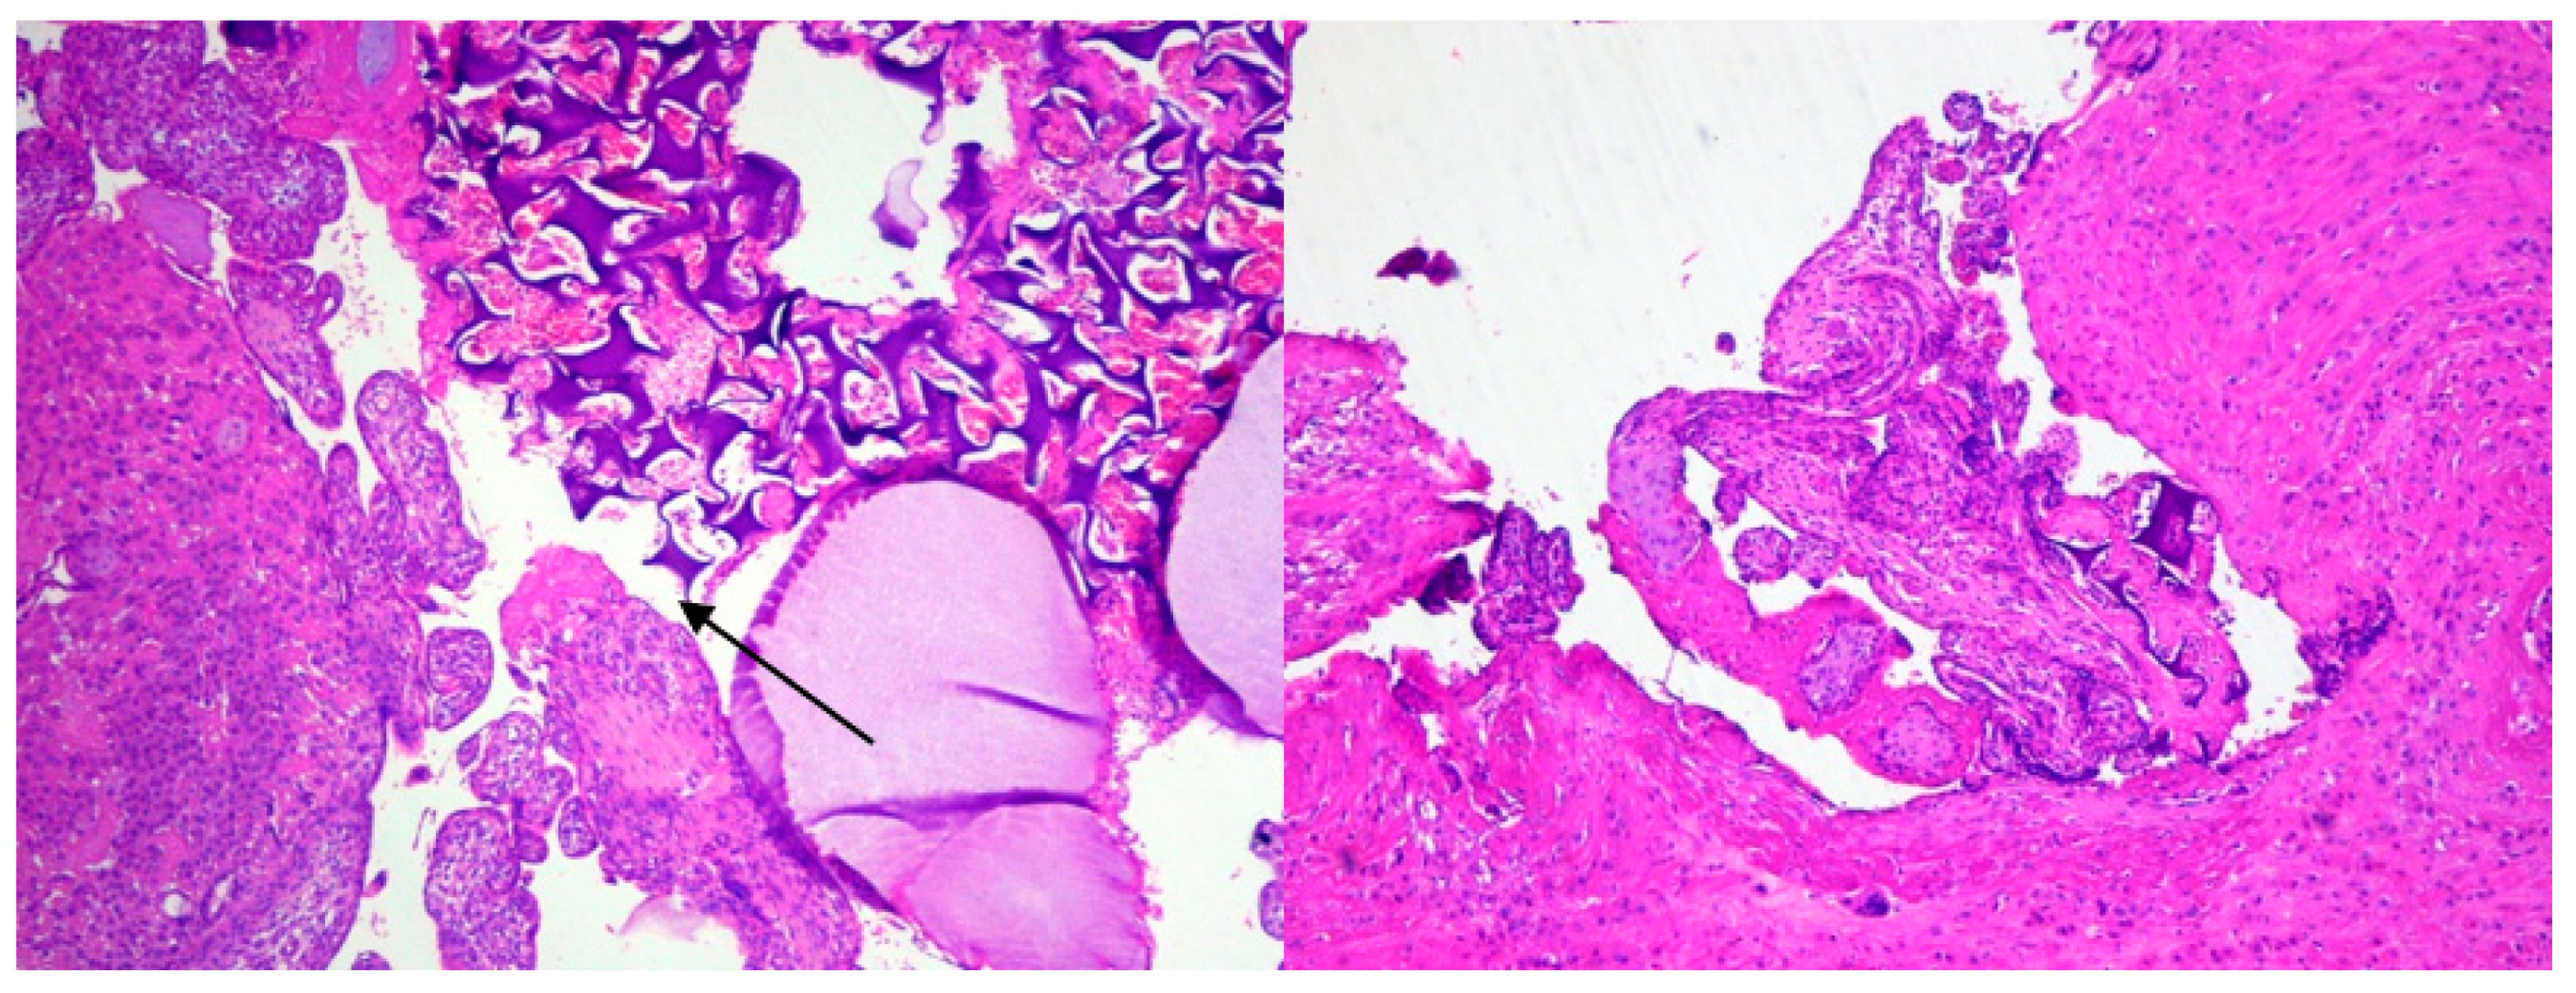

1.2. Case 2

2. Discussion